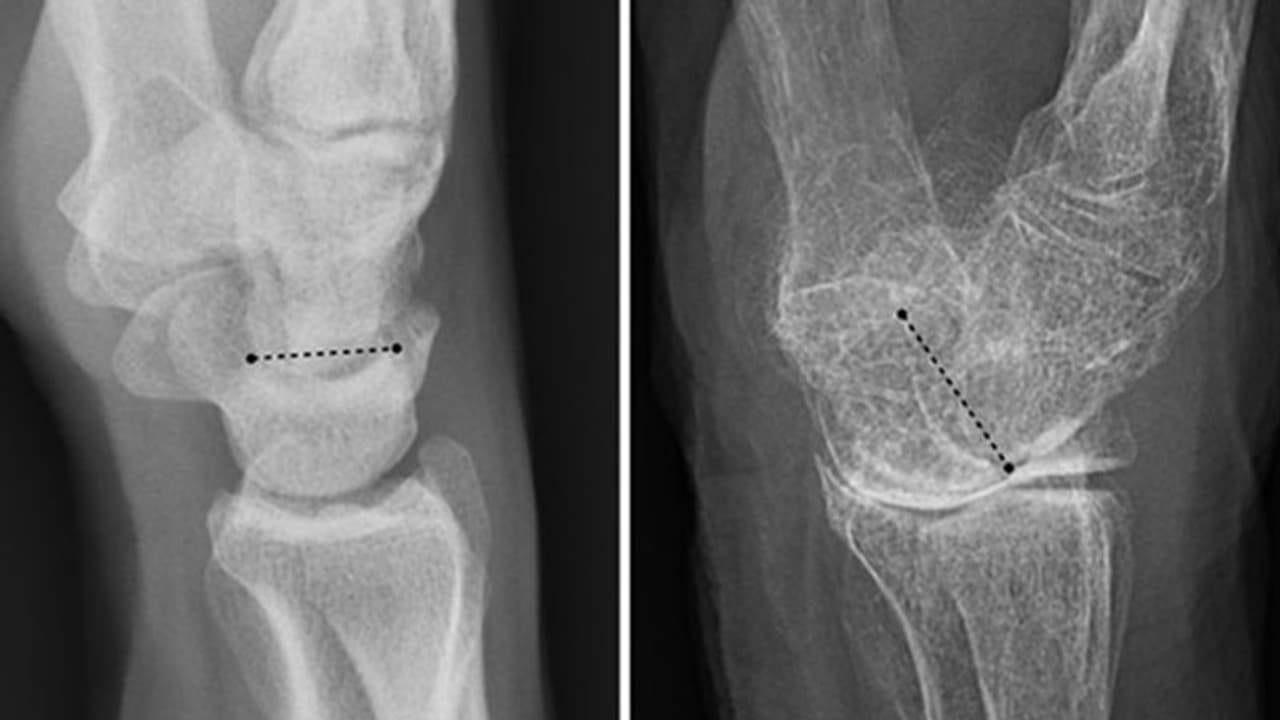

വളരെ പതുക്കെ അസ്ഥികൾക്കുണ്ടാകുന്ന ഈ വൈകല്യം എല്ലുകളുടെ തേയ്മാനത്തിനും ബലക്ഷയത്തിനും പൊട്ടലിനും കാരണമാകുമെന്നാണ് വിദഗ്ധർ പറയുന്നത്. പ്രായമാകുമ്പോൾ ചെറുതായി ഒന്ന് കാല് തെന്നിയാൽ പോലും വലിയ രീതിയിൽ എല്ലുകൾ പൊട്ടുന്നതിലേക്ക് നയിക്കുന്നത് ഓസ്റ്റിയോ പൊറോസിസാണ്.

പുരുഷന്മാരെക്കാൾ സ്ത്രീകളിലാണ് ഈ രോഗം കൂടുതലായി കണ്ട് വരുന്നത്. ആർത്തവ വിരാമത്തോടു കൂടി സ്ത്രീകളിലുണ്ടാകുന്ന ഹോർമോൺ വ്യതിയാനങ്ങളാണ് കാരണം. ഈസ്ട്രജൻ കുറയുന്നത് അസ്ഥിയുടെ കട്ടി കുറയാൻ കാരണമായി തീരുന്നു. സ്ത്രീകളിലെ ഇടുപ്പ്, കൈക്കുഴ, നട്ടെല്ല് എന്നീഭാഗങ്ങളിലെ വേദനയ്ക്കെല്ലാം ഓസ്റ്റിയോ പൊറോസിസ് കാരണമാകാം.